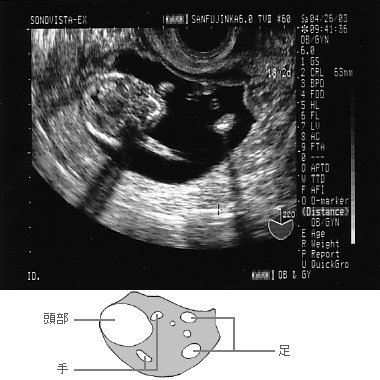

![]() 2003年5月2日、14週4日のちびちゃん。 BPD(児頭大横径:biparietal diameter)=31mm、1日分大きい。 左の丸い部分が頭、その右に続いて胴体、胴体のわきの丁度肩あたりの位置に肩。 腰のあたりまでが写ってるわけかな。 |